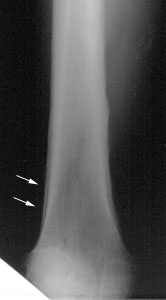

Plain film findings in HOA reveal a smooth, thick, linear,

lamellar periosteal new bone

formation along the shafts of tubular bones sparing the

epiphyses (epiphyseal involvement is more common with primary

HOA [34]). The tibia, fibula, radius, and ulna are the most

commonly affcted bones, followed by the phalanges of the fingers

[34]. Bone scan may show symmetric patchy or linear increased

activity along the periosteum of

long bones- termed the tram line or double stripe sign [34].